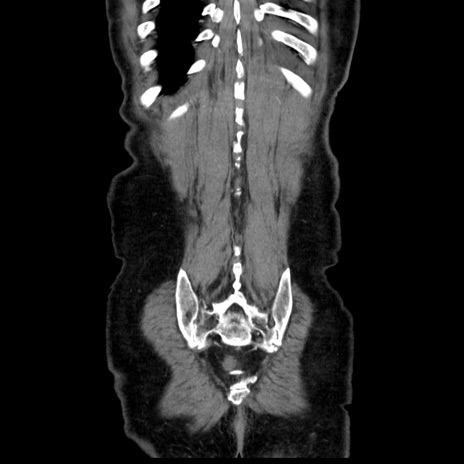

症例30(冠状断像)

【症例】80歳代男性

【主訴】臍周囲痛

【現病歴】約6時間前から臍下部痛が出現。次第に腹部膨隆・背部痛も生じてきたため来院。背部痛の場所は変化しない。

【身体所見】意識清明、BT 36.3℃、BP  131/87mmHg、P 87bpm、SpO2 100%(RA)、臍周囲自発痛・圧痛あり、反跳痛なし、自発痛部位に一致して板状硬あり、腹部膨隆、腸雑音減弱、CVA tenderness両側陰性。

【データ】WBC 19600、CRP 0.33